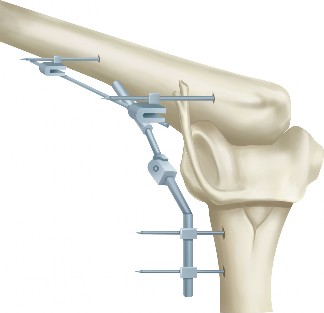

The correct answer is (A). Massive and immobile tears can be either U-shaped or longitudinal. These can sometimes be repaired using an anterior or posterior

interval slide technique. In an anterior interval slide technique, there is some anterior portion of the supraspinatus still attached to the greater tuberosity laterally and rotator interval anteriorly. The greater tuberosity attachment can be incised and the rotator interval attachment can be detached by incising the coracohumeral ligament. In a posterior interval slide technique, there is some posterior portion of the supraspinatus still attached to the infraspinatus. This can be detached by incising the interval between the supraspinatus and infraspinatus (Answer B). These interval slide techniques decrease the tension and improve lateral mobilization, allowing the supraspinatus to be more easily repaired to the greater tuberosity. The posterior leaf of the tear is then brought together with the anterior leaf through marginal convergence, leaving you with a small crescent-shaped tear that can be repaired to the greater tuberosity (see Fig. 2–16).

Figure 2–16_Massive, immobile rotator cuff tear and repair using anterior interval slide followed by marginal convergence. SS, supraspinatus; IS/TM, infraspinatus/teres minor; RI, rotator interval; CHL, coracohumeral ligament; Sub, subscapularis. (Redrawn from Burkhart SS, Lo IKY. Arthroscopic rotator cuff repair. J _Am Acad Orthop Surg. 2006;14(6):333–346.)